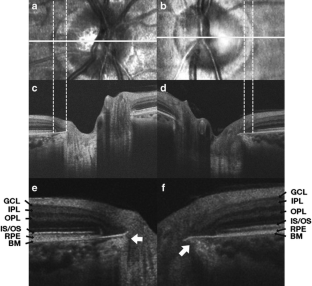

Fifty young myopic eyes with PPA (myopic PPA group), 50 aged non-myopic eyes with PPA (aged PPA group), and 50 young non-myopic eyes without PPA (control group) were enrolled. High-definition OCT scanning was used to obtain horizontal cross-sectional optic nerve head (ONH) images. By use of these OCT scans we investigated three temporal optic disc margin structures: the configuration of the border tissue of Elschnig; the cross-sectional ONH structure coinciding with the clinically detected optic disc margin; and the integrity of the retinal layers within the PPA area.

The distribution of the configuration of the border tissue of Elschnig and the cross-sectional ONH structure coinciding with the clinically detected optic disc margin of the myopic PPA group differed significantly from those of the control group (P < 0.01) whereas those of the aged PPA group did not (P > 0.05). Other than the photoreceptor layer, the retinal layers within the PPA area were more commonly impaired in the myopic PPA group than in the aged PPA group (P < 0.001).

Fig. 1